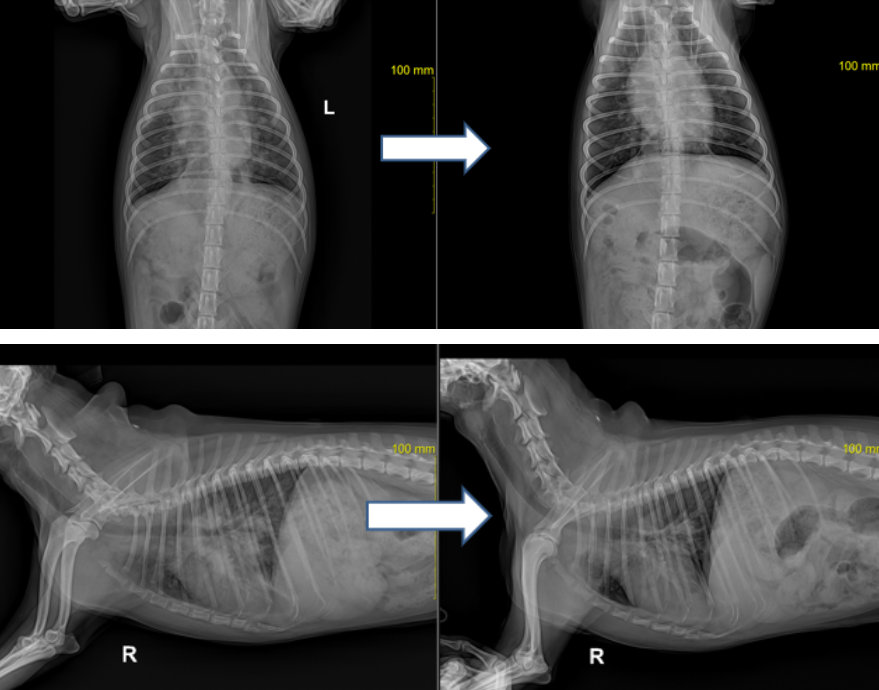

흉부방사선 상에서 폐전엽에 걸친 침윤이 있었으며 복배상에서는 결절로 의심되는 부분도 확인되었습니다. ▼

스테로이드와 항생제 그리고 수액처치 후 환자의 개선속도는 급격하게 좋아졌으며

기침 호흡곤란 증상도 매우 좋아졌습니다. (방사선은 치료 후 3일 경과 사진) ▼